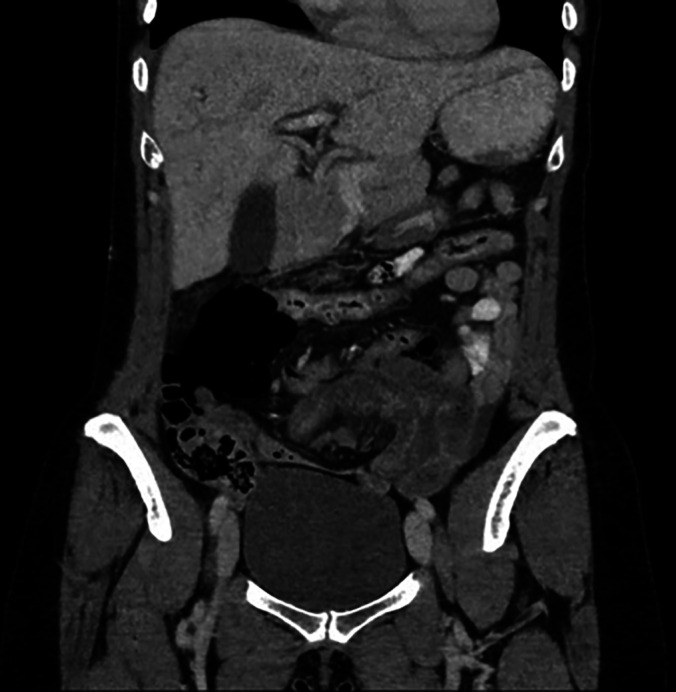

Case description: We treated a 42-year-old female airline cabin crew member who presented with colicky abdominal pain, bilious vomiting, and lower abdominal tenderness. Her abdominal computed tomography (CT) scan showed small bowel obstruction with loops of small bowel predominantly in the left lower abdomen. She had a history of a single episode of similar abdominal pain many years prior, which resolved spontaneously. The rest of her history was unremarkable. She received nonoperative management initially, but due to persistent abdominal pain and vomiting, a diagnostic laparoscopy was done. The diagnostic laparoscopy showed congested but viable small bowel herniating into a peritoneal defect through the lateral part of left broad ligament at the lateral pelvic wall into the retroperitoneum. The hernia was reduced, and the defect was repaired. Postoperatively, she had an uncomplicated recovery.